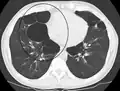

A realização de uma radiografia ao tórax e de um hemograma permitem excluir outras condições no momento do diagnóstico.[69] Os sinais característicos da DPOC observáveis em radiografia são pulmões sobre-expandidos, diafragma achatado e espaço retroesternal aumentado. Ao mesmo tempo, a radiografia permite excluir outras doenças pulmonares, como pneumonia, edema pulmonar ou pneumotórax.[70] Uma tomografia axial computorizada ao tórax permite mostrar a distribuição do enfisema pelos pulmões e pode ajudar a excluir outras doenças pulmonares.[18] No entanto, a não ser nos casos em que se planeie a realização de uma cirurgia, esta distribuição raramente influencia o tratamento.[18] Pode ainda ser realizada uma gasometria arterial para determinar a necessidade de oxigénio suplementar. Este exame é recomendado em pessoas com VEF1 inferior a 35% do previsto, com saturação periférica de oxigénio inferior a 92% e pessoas com sintomas de insuficiência cardíaca congestiva.[17] Em regiões do mundo onde é comum a deficiência de alfa-1 antitripsina, as pessoas com DPOC devem considerar a realização deste exame, sobretudo aquelas com idade inferior a 45 anos e em que o enfisema afeta a parte inferior dos pulmões.[17]

- Radiografia torácica de DPOC grave, em que se observa o tamanho relativamente pequeno do coração em relação aos pulmões.

- Radiografia torácica lateral de pessoa com enfisema, em que se observa tórax em tonel e diafragma achatado.